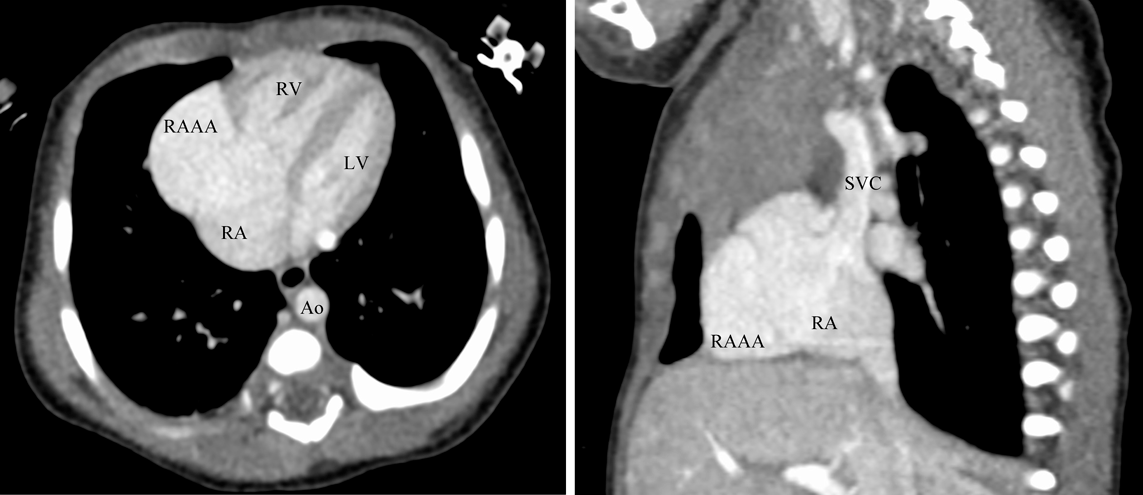

胎児期に診断し,無治療で経過観察できている先天性右心耳瘤の一例A Case of Congenital Right Atrial Appendage Aneurysm Diagnosed Prenatally and Followed-Up Without Treatment